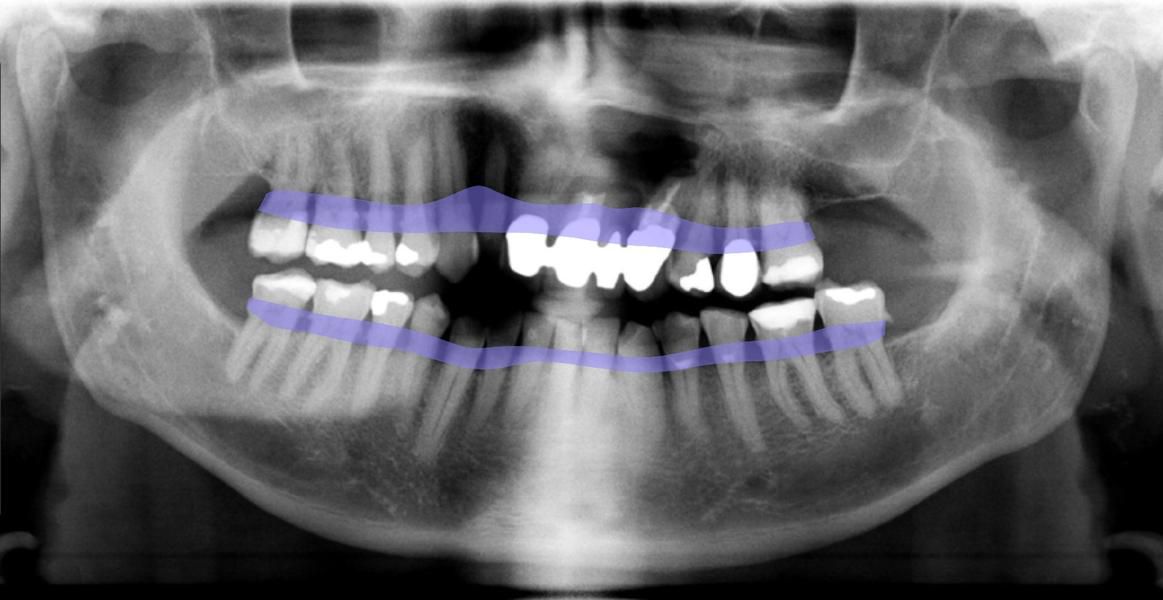

Das „OPG“ wird bei der Aufnahme direkt in der EDV gespeichert und bietet uns einen Überblick über den gesamten Kieferbereich.Es bietet sehr viele diagnostische Möglichkeiten der Krankheitserkennung und auch der Implantatplanung.

Technisch ist unsere Zahnarztpraxis stets am Puls der Zeit. Daher freuen wir uns, dass wir jetzt auch zu den Ersten gehören, die bei der zahnmedizinischen Diagnostik auf das KI-unterstützte Tool dentalXrai setzen. Die aus der Berliner Charité entwickelte Software ermöglicht uns eine sichere automatisierte Analyse zahnmedizinischer Röntgenbilder – und zwar in Sekundenschnelle. Die Bestätigung der ärztlichen Befundung durch die KI-Lösung schafft zudem mehr Sicherheit und Vertrauen.

„Mit dem neuen Tool sparen wir nicht nur wertvolle Arbeitszeit, sondern können unsere Patienten noch besser in die Diagnose einbeziehen. Die Röntgenbilder zeigen wir ihnen ab sofort einfach am iPad, das Tool dentalXrai markiert hier Infektionen und Karies farbig. So sind Röntgenbilder und die Diagnose für jedermann leicht zu verstehen“, erklärt ZA Klaus Kirste die Beweggründe, dentalXrai in der Praxis einzuführen.

Die Röntgenbilder können im Anschluss dann einfach als PDF an unsere Patienten versendet werden.